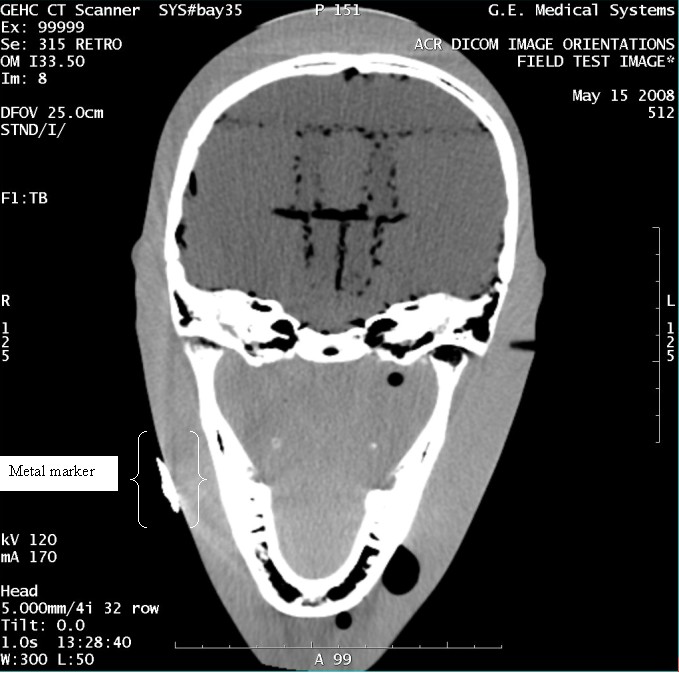

- With the support of the site personnel, examine the images sent

to the Review Station (i.e., 12 series, each with 1 image) and compare

their orientation to the images in this document.

- Each image contains a metal marker on the phantom's right cheek.

- Each image in this document contains a description of the expected

orientation of the metal marker (i.e. to prove Left and Right) as

well as the Posterior and Anterior orientation description.note:

The sample images included in this document use “R”, “L”, “P”, and “A” for “Right”, “Left”, “Posterior” and “Anterior” orientation. The Hospital Review Station may use a different style of annotation. The style used is not relevant to this procedure.

Figure 4. Exam 99999, Series 315